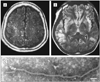

The first part of this review ended with a discussion of new niches for known viruses as illustrated by viral central nervous system (CNS) disease associated with organ transplant and the syndrome of human herpesvirus 6-associated posttransplant acute limbic encephalitis. In this part, we begin with a continuation of this theme, reviewing the association of JC virus-associated progressive multifocal leukoencephalopathy (PML) with novel immunomodulatory agents. This part then continues with emerging viral infections associated with importation of infected animals (monkeypox virus), then spread of vectors and enhanced vector competence (chikungunya virus [CHIK]), and novel viruses causing CNS infections including Nipah and Hendra viruses and bat lyssaviruses (BLV).